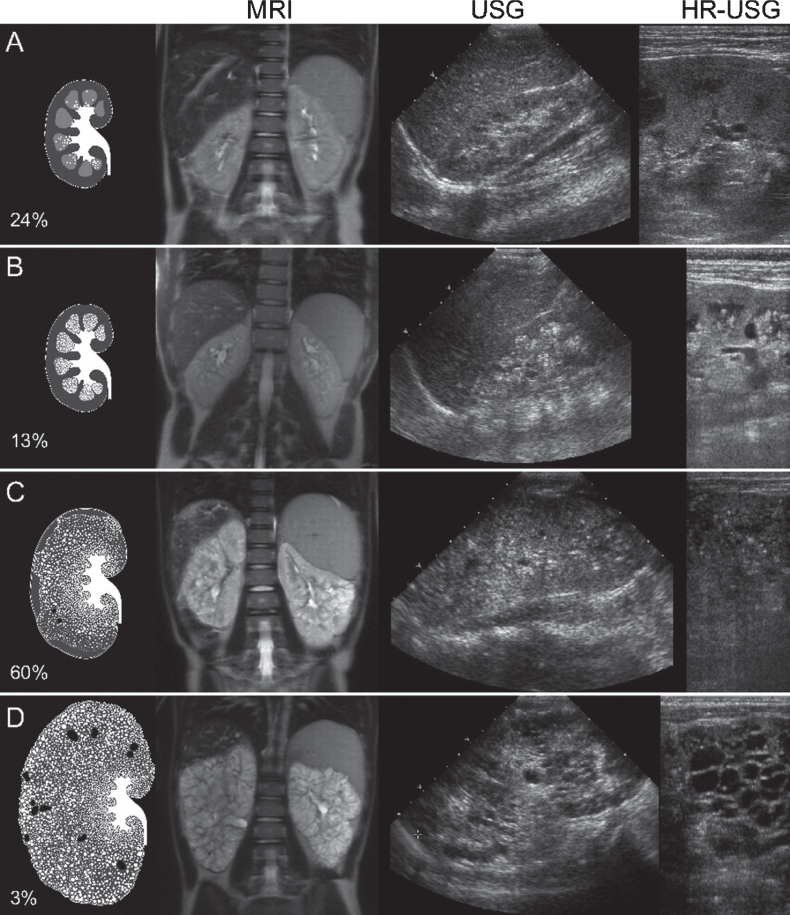

Abstract Image